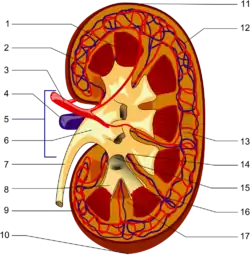

The renal column (or Bertin column, or column of Bertin) is an extension of the renal cortex in between the renal pyramids. It allows the cortex to be better anchored. (Cortical extensions into the medullary space.)

Each column consists of lines of blood vessels and urinary tubes and a fibrous material.

A hypertrophied renal column (or renal pseudotumor) may be differentiated from an actual renal tumor with the help of a DMSA scan. The scan will show the area as one with normal activity if it is a pseudotumor or will show decreased uptake if it is a cystic or solid renal mass.